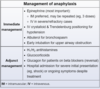

Out of the Tx for COPD Exacerbation

Which improves survival?

________________

Which ⬇︎future events?

“I’m having COPD Exacerbation! Give me DOPA! (but not really)”

[O2 PRN via BiPAP (goal: 90-94% O2 Sat)]

________________

Abx (Azithro-⬇︎future events or Levoflox or Doxy)

Tx for COPD Exacerbation-4

“I’m having COPD Exacerbation! Give me DOPA! (but not really)”

- Duoneb (albuterol + ipratropium)

- O2 PRN via BiPAP (goal: 90-94% O2 Sat)

- [Prednisone 40 mg qd x 5]

- Abx (Azithro-⬇︎future events or Levoflox or Doxy)